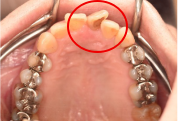

女性 Kさん 30代 (オールセラミック冠・オールセラミックブリッジ)

主訴

上前歯をきちんときれいに治したい。(仮歯のままのところもあります)

治療内容

4本の歯、すべて根管治療をし、オールセラミックのブリッジとオールセラミック冠を被せました。

所感

患者さんは、前の医院に不満を抱き、転院されてきました。前の先生の意図を理解できませんが、いろいろな歯の治療が中途半端な状態でした。根管治療が不備な歯があり、根尖に病巣を作っていましたので、一つ一つ根管治療をしていきました。完成の前の試適の時に、技工士さんに来ていただきました。色および形を患者さんに見ていただき、希望を十分にお聞きし、患者さん・私・技工士さん3人の目で見てバランスよく仕上げて完成にしました。

オールセラミック冠4本:¥104,500×4本=¥418,000(税込)

オールセラミックポンティック:¥93,500×1本=¥93,500(税込)

合計:¥511,500(税込)